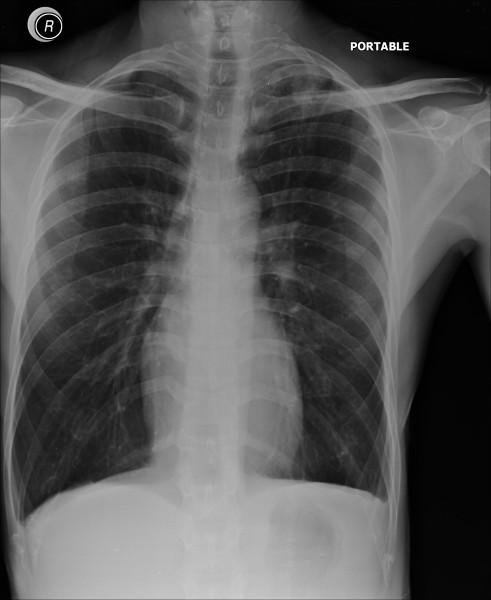

Pneumothorax

Tension pneumothorax

Pleural effusion